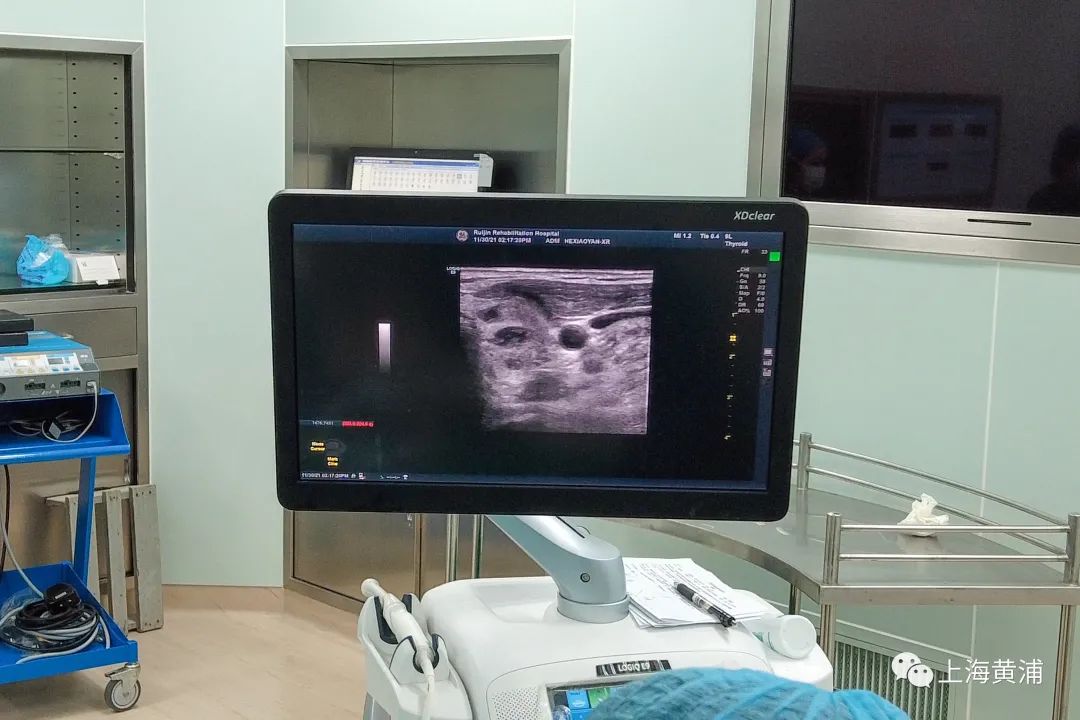

顾建华认为,产生结节的因素非常多,从他多年临床经验来看,有一些是可以在日常生活中去干预的:一个是调节日常生活节奏,还有就是尽量减少射线照射。当然,定期超声体检必不可少,这是诊断结节最直接的方法,“一些微小的结节我们可以通过穿刺、基因检测、细胞学等检查及早诊断,并尽早治疗。”

据顾建华介绍,瑞康医院最为擅长的有甲状腺开放手术、甲状腺腔镜手术及甲状腺的超声介入下消融,“甲状腺开放手术通常用于甲状腺癌,通常指大于等于5毫米的甲状腺恶性肿瘤,其中包括甲状腺癌根治术、甲状腺癌扩大根治术、颈部淋巴结清扫术,这些通过手术都可以达到治愈的目的。”目前,瑞康医院对甲状腺疾病患者采用“一人一方”,即对患者不同程度的疾病给予个体化的诊疗方案,“对于有些被诊断为恶性肿瘤的微小甲状腺结节,我们可以通过腔镜或超声下消融技术去治愈,这样不但可以保住甲状腺的功能,还能保证颈部的美观。”

而对于患者在3厘米至5厘米之内的良性结节,瑞康医院则会采取超声引导下消融技术,不需要开刀就能保住颈部的美观,又能够使甲状腺的功能得以保留。